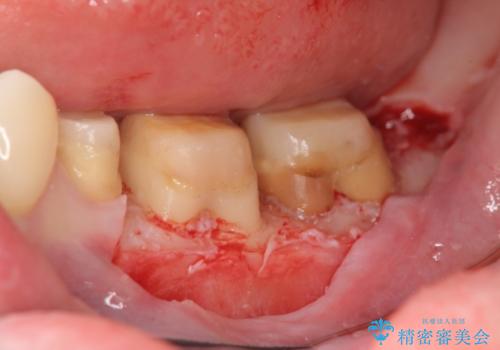

現在装着されているクラウンを除去したところ、クラウンマージンが歯肉縁下となり歯ぐきの炎症が認められたため再度オールセラミッククラウンを製作する前に歯周外科手術を行い歯ぐきの状態を改善しました。

歯ぐきに起きる炎症は、歯ブラシの不足によるプラークによる炎症の他、歯周病、深い虫歯などの原因により惹起されます。